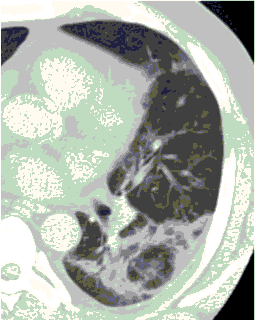

4.3. ЛУЧЕВАЯ ДИАГНОСТИКА COVID-19

Методы лучевой диагностики применяют для выявления COVID-19 пневмоний, их осложнений, дифференциальной диагностики с другими заболеваниями легких, а также для определения степени выраженности и динамики изменений, оценки эффективности проводимой терапии.

Лучевые методы также необходимы для выявления и оценки характера патологических изменений в других анатомических областях и как средства контроля для инвазивных (интервенционных) медицинских вмешательств.

К методам лучевой диагностики патологии ОГК пациентов с предполагаемой/установленной COVID-19 пневмонией относят:

- Обзорную рентгенографию легких (РГ),

- Компьютерную томографию легких (КТ),

- Ультразвуковое исследование легких и плевральных полостей (УЗИ).

Стандартная РГ имеет низкую чувствительность в выявлении начальных изменений в первые дни заболевания и не может применяться для ранней диагностики. Информативность РГ повышается с увеличением длительности течения пневмонии. Рентгенография с использованием передвижных (палатных) аппаратов является основным методом лучевой диагностики патологии ОГК в ОРИТ. Применение передвижного (палатного) аппарата оправдано и для проведения обычных РГ исследований в рентгеновском кабинете. В стационарных условиях относительным преимуществом РГ в сравнении с КТ являются большая пропускная способность. Метод позволяет уверенно выявлять тяжелые формы пневмоний и отек легких различной природы, которые требуют госпитализации, в том числе направления в ОРИТ.

КТ имеет высокую чувствительность в выявлении изменений в легких, характерных для COVID-19. Применение КТ целесообразно для первичной оценки состояния ОГК у пациентов с тяжелыми прогрессирующими формами заболевания, а также для дифференциальной диагностики выявленных изменений и оценки динамики процесса. КТ позволяет выявить характерные изменения в легких у пациентов с COVID-19 еще до появления положительных лабораторных тестов на инфекцию с помощью МАНК. В то же время, КТ выявляет изменения легких у значительного числа пациентов с бессимптомной и легкой формами заболевания, которым не требуется госпитализация. Результаты КТ в этих случаях не влияют на тактику лечения и прогноз заболевания при наличии лабораторного подтверждения COVID-19. Поэтому массовое применение КТ для скрининга асимптомных и легких форм болезни не рекомендуется. При первичном обращении пациента с подозрением на COVID-19 рекомендуется назначать КТ только при наличии клинических и инструментальных признаков дыхательной недостаточности (SpO2 < 95%, ЧДД > 22).